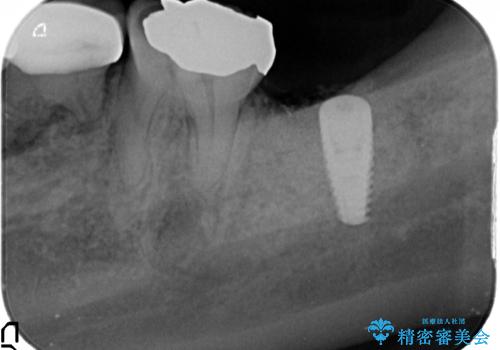

最後方臼歯周囲には大きな透過像が見られ、破折が強く疑われること抜歯が想定されることを理解していただき銀歯を除去したところ破折が認められたため抜歯を行いました。

良好なインプラントの植立を行うためには、十分な骨量があることが必須条件です。

術前、歯の破折により大きな骨の吸収が認められていたため骨量を十分に回復するために抜歯と同時に歯槽堤保存術を行い十分な骨量の回復をすることができました。